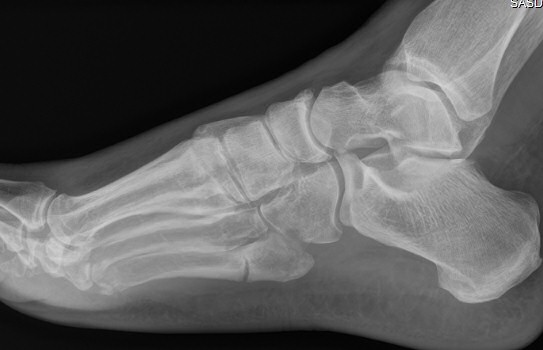

Exempel på Jones-frakturer, första bilden färsk, andra bilden ej läkt, tredje bilden efter operation.